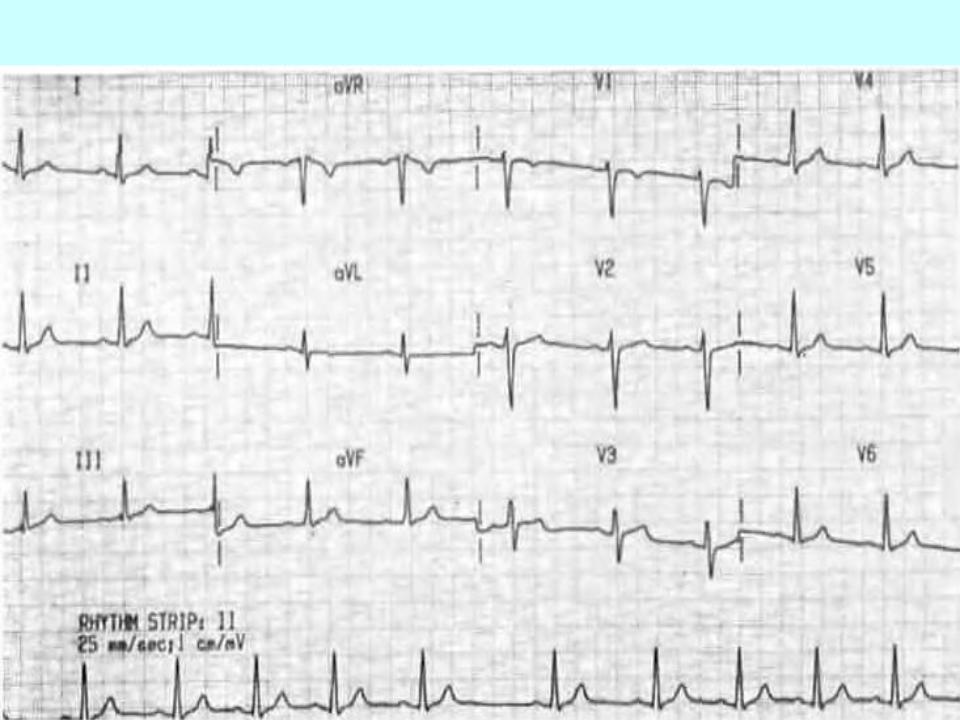

Sinus bradycardia:

The main ECG signs:

1.The P wave in all cardiac cycles precedes complex QRS, its form is constant in each lead.

2.The duration of the interval P-Q (R) is the same in all complexes.

3.Different intervals R-R (P-P), and this the difference is greater than 10% of the average R-R distance (R-R), usually about 12-0.15 C and more.